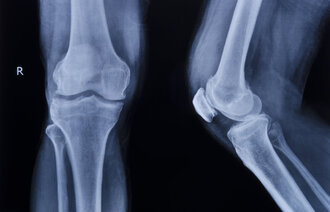

Ved det store ortopediske sykehuset RNIITO (Vreden Russian Research Institute of Traumatology and Orthopedics) i St. Petersburg, har Lindberg, sammen med blant andre UiO-professor Anners Lerdal, bidratt til en studie av smerteforløp, funksjon og livskvalitet hos pasienter som gjennomgår kneproteseoperasjoner.

Fra russisk side har lederen av knekirurgiavdelingen ved RNIITO, ortopeden Nickolay Kornilov, vært ansvarlig for gjennomføringen av studien, som er basert på en tilsvarende undersøkelse Lindberg ledet ved Lovisenberg Diakonale Sykehus i Oslo.

I grove trekk viste studien svært høy smerteintensitet hos pasientene. Lengre operasjonstid ga høyere smerteintensitet i etterkant, og studien konkluderte med at smertebehandlingen som ble gitt, var mangelfull.